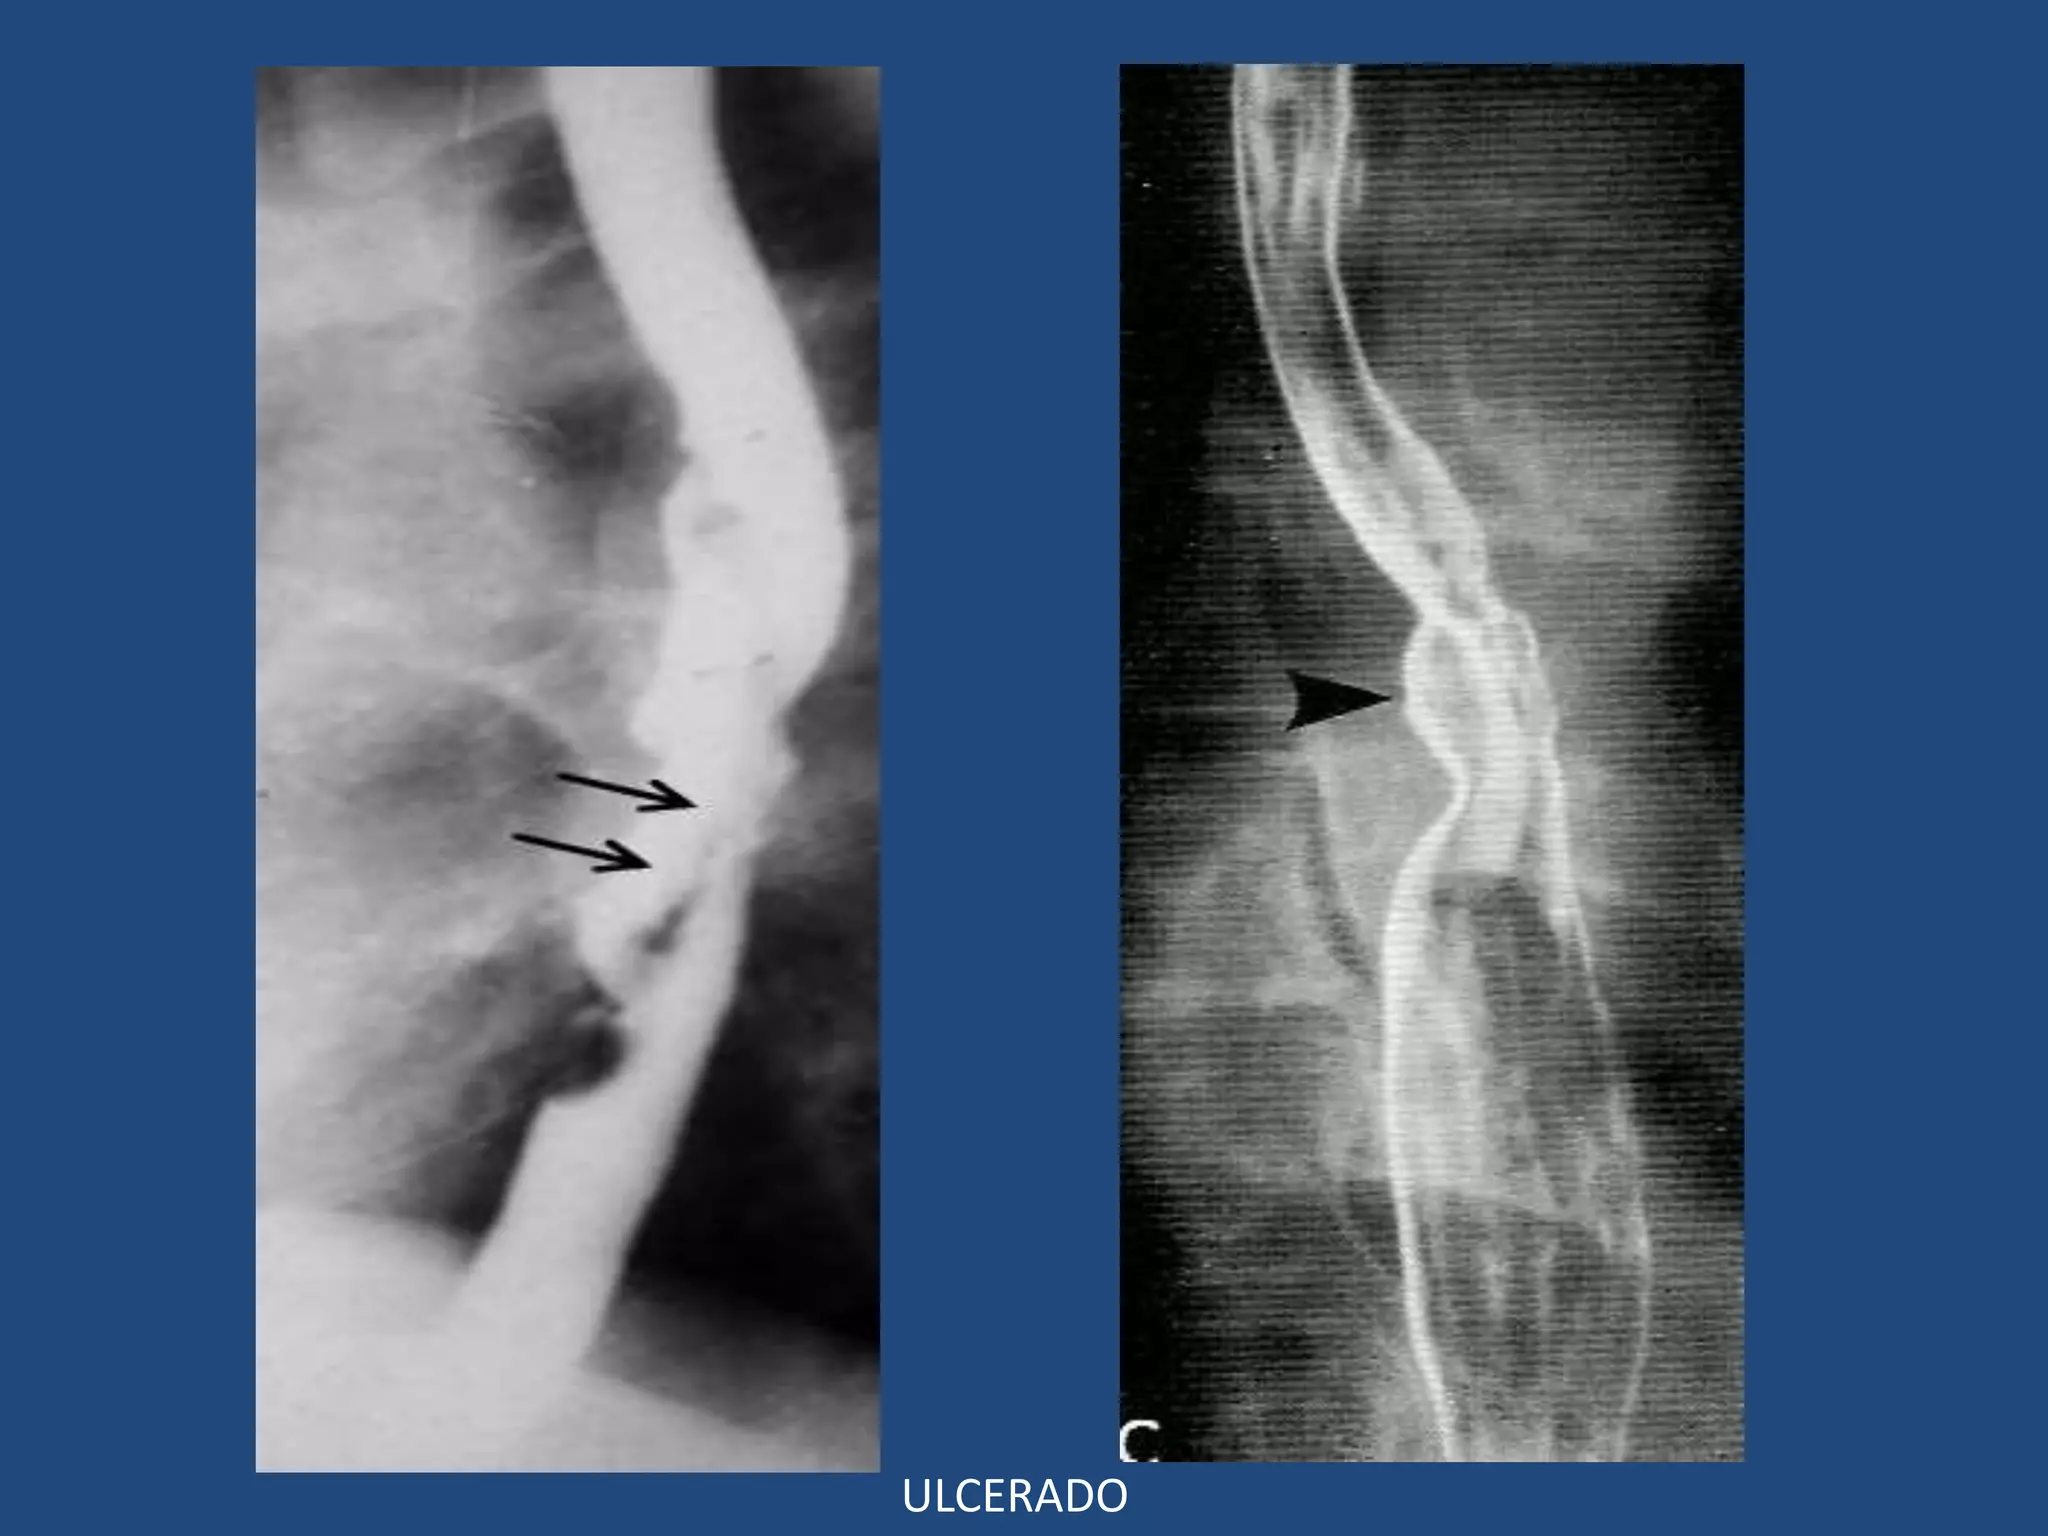

ESÓFAGO: TUMORES MALIGNOS

Hallazgos tempranos:

- Inicia como un pólipo aplando sésil o placa

aplanada sobre la pared.

- Pequeña ulcera central

- Rigidez de la pared (difícil dx dif con lesiones

benignas).

Placa aplanada Ulceración

Ca temprano = pólipo

Ca temprano = Placa

• Hallazgos Avanzados:

3 Patrones típicos simples o combinados:

- Polipoide

- Infiltrante

- Ulcerado

POLIPOIDEA

INFILTRANTE

ULCERADO

Ulceración

Infiltrativo

MIXTO